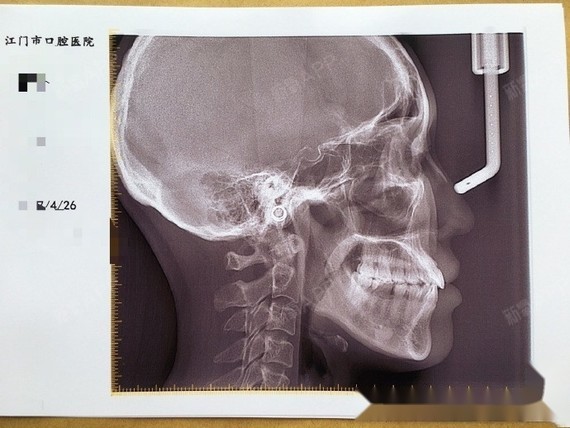

矫正年龄:33岁

矫正时间:一年十个月

牙齿情况:地包天,有骨性

方案:戴钢牙套,没有拔牙,费用是11000左右

我们先来看看地包天矫正后的侧脸前后对比变化,地包天改善后原来的“月牙脸”不见了,现在侧脸美美哒~